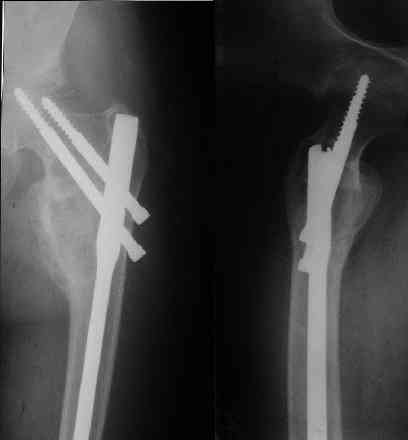

Под рукой нашелся повод для похожих эмоций. Патологический перелом на месте рецидива костной кисты у девочки 16 лет (обсуждали этот случай

года два назад). Ни коллапана, ни трансплантатов, ничего другого в очаг не вводили, кроме нержавеющей стали. Она, видимо, тоже остеоиндуктор - видно, что на месте пустоты через несколько месяцев кость.

Согласен на все сто с Вашей последней фразой. Не знаю как учат сейчас врачей в ВУЗАХ, но по-моему основы доказательной медицины познаются уже в процессе работы. А что касается Вашего примера, то давно известно, что кистозные опухоли у детей могут спонтанно регенерировать после перелома. Пример рецидива кисты после неадекватной пластики Вы видите на этой же странице. По поводу РФ не могу судить, но в Казахстане больше применяют стоматологи для подготовки к импланатации протезов при дефектах костей челюсти. Спасибо за обсуждение темы.